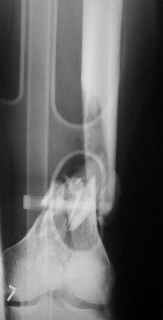

Open supracondylar femur fx

What would be your method of choice to fix this Gr IIIa open high energy supracondylar femur fx, neuro vasculary intact.

30 YO male MBA hemodynamically stable, no chest injuries. Right temporal bone fx, no IC bleeding on the head CT. Images attached. Best Regards, Zsolt Balogh, MD Trauma Surgeon Szeged, Hungary